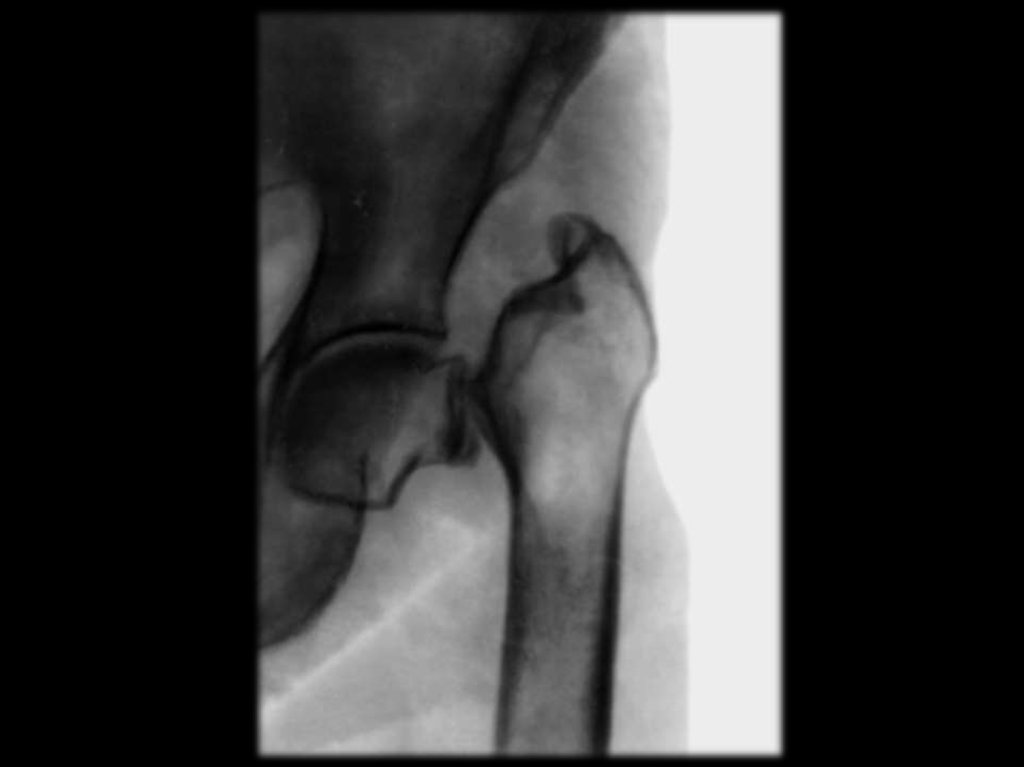

15. Локализация переломов

Шейка бедра